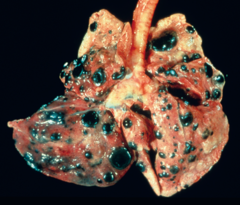

spleen

Front

kidney